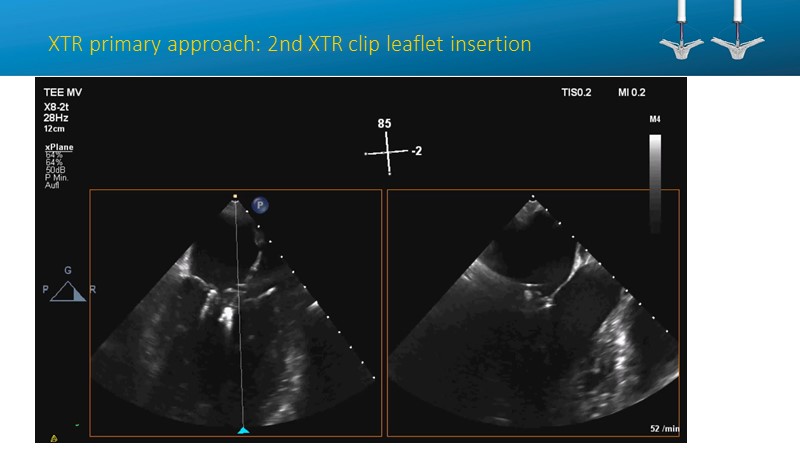

- To learn how will product innovation (Mitraclip NTR / XTR) drive improvement in procedural and clinical outcomes (EXPAND)